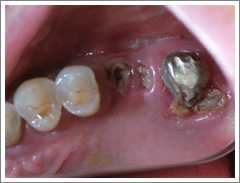

症例 6 虫歯によって失った下の奥歯に対してインプラント治療を行ったケース

治療前

むし歯によって失ってしまった右下の2本の奥歯にインプラント治療を行った症例です。 インプラント治療によってしっかりと咬むことができるようになり、左右でバランスよく咬んで食事をすることができるようになりました。 ( 70代 女性 )